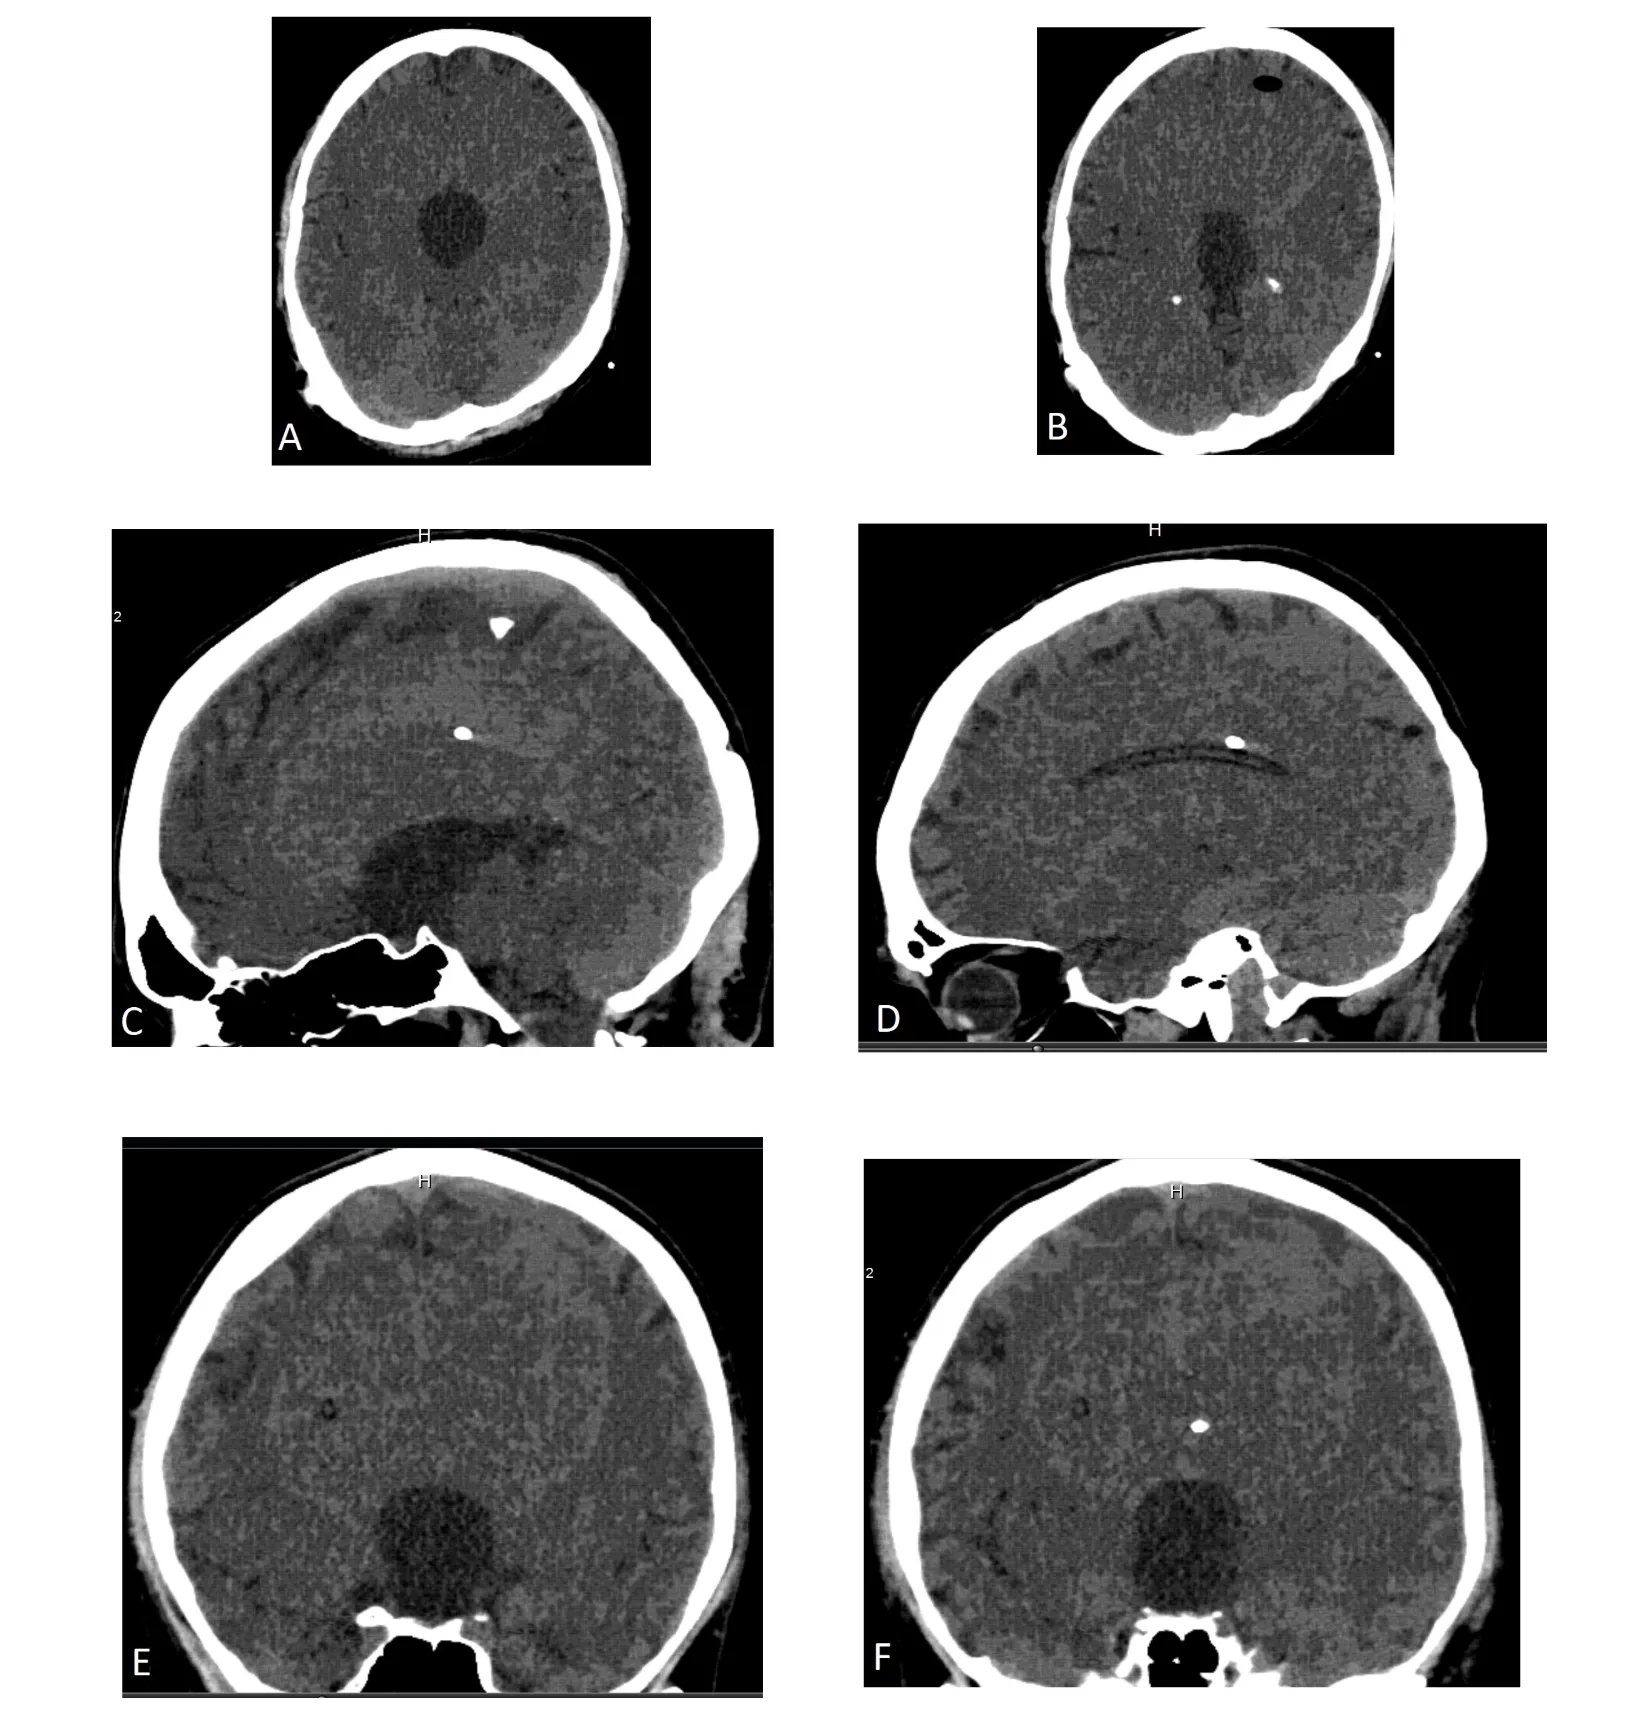

CT ventriculogram demonstrated a trapped third ventricle secondary to bilateral foramen of Monro obstruction or occlusion, with intact fourth ventricle. Figure 1 shows cranial CT with triventricular hydrocephalus and right VP shunt. The contrast dye placed in the frontal horn of lateral ventricle was not seen entering the third ventricle at all, even on follow up scans shown in Figures 2 and 3. No contrast egress was noted into the rounded enlarged third ventricle. Eventually the dye cleared off the lateral ventricles as demonstrated in Figure 4 done 24 hours after contrast injection. Given the fact that the patient improved neurologically and there was a possibility of arrested hydrocephalus, he was started on a higher dose of Keppra and he was discharged home at his neurologic baseline exam.

It is important to note that any reduction in the VP shunt setting would have led to an overdrainage subdural hematoma, and a trial of CSF drainage via EVD or externalization of existing VP shunt even would have probably led to an overdrainage of ventricular CSF. This case is a perfect example where any surgical intervention would have been riskier than masterly inactivity, and his subsequent head CT scans for active annual surveillance has shown no increase or decrease in ventricular size over the next three years to follow.